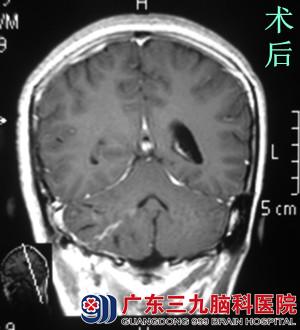

行MR检查提示右侧小脑半球囊性伴有壁结节占位性病变,大小约4.5*3.7*3.2cm,考虑血管母细胞瘤可能性大。完善相关检查后,由鲁明主任主刀,在全麻下行右侧小脑半球血管母细胞瘤切除术,术中显微镜下见囊内灰褐色结节,予镜下完整切除,手术顺利结束。术后病理:术后经过专科治疗护理,小陈术前症状基本消失,康复出院。